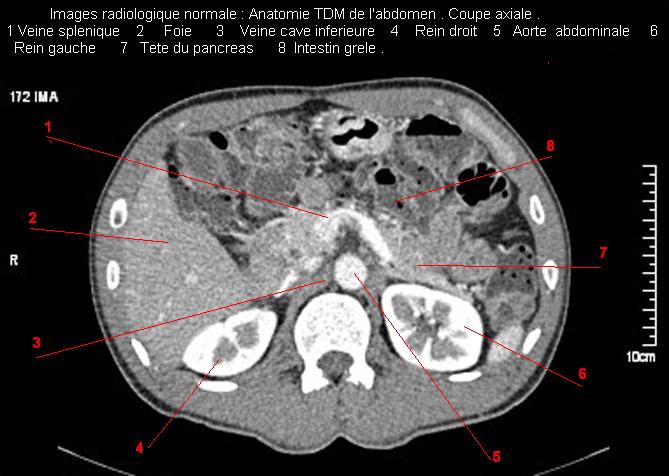

Images radiologique TDM normale de abdomen et tube digestif en coupe axiale ( CT scanner )  :

Coupe axiale     Coupe frontale      Coupe  sagitale